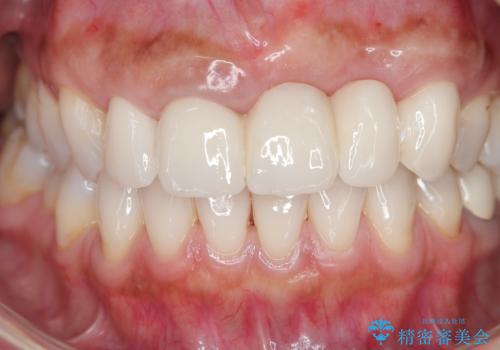

歯槽堤保存術を併用したブリッジ治療

抜歯時に可及的に歯肉のボリュームを保つよう骨充填材とコラーゲン製剤による填塞を行い審美的かつ機能的なブリッジとなるよう治療を進めます。

- 66万円(ジルコニアクラウン×5・仮歯×5)費用は治療当時の料金となります

一件綺麗に見えるセラミックも適合や精度が悪いと、内部で虫歯が進行し亀裂や破折、悪臭の原因となることがあります。